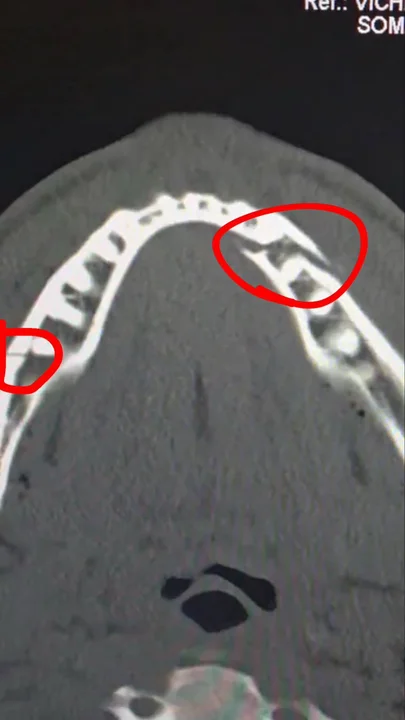

Tras la pelea, se confirmó que Jake Paul sufrió una doble fractura de mandíbula, producto de la potencia del ex campeón mundial. A pesar de la gravedad de la lesión, Paul mantuvo su estilo desafiante en redes sociales: